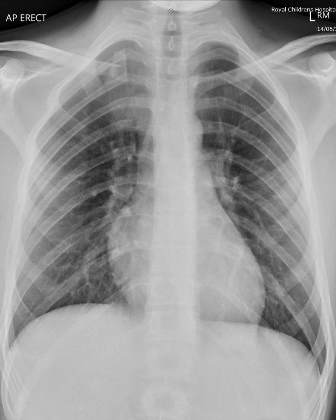

A Contrast CT with 3D CT reconstruction scan (Fig. 2, 3), confirmed the alignment of the floating fragment (rotated and with its medial end pointing posteriorly), which was causing compression on the right Brachiocephalic vein.

Fig. 2: Axial section from Contrast CT Scan showing compression of fracture on brachiocephalic vein